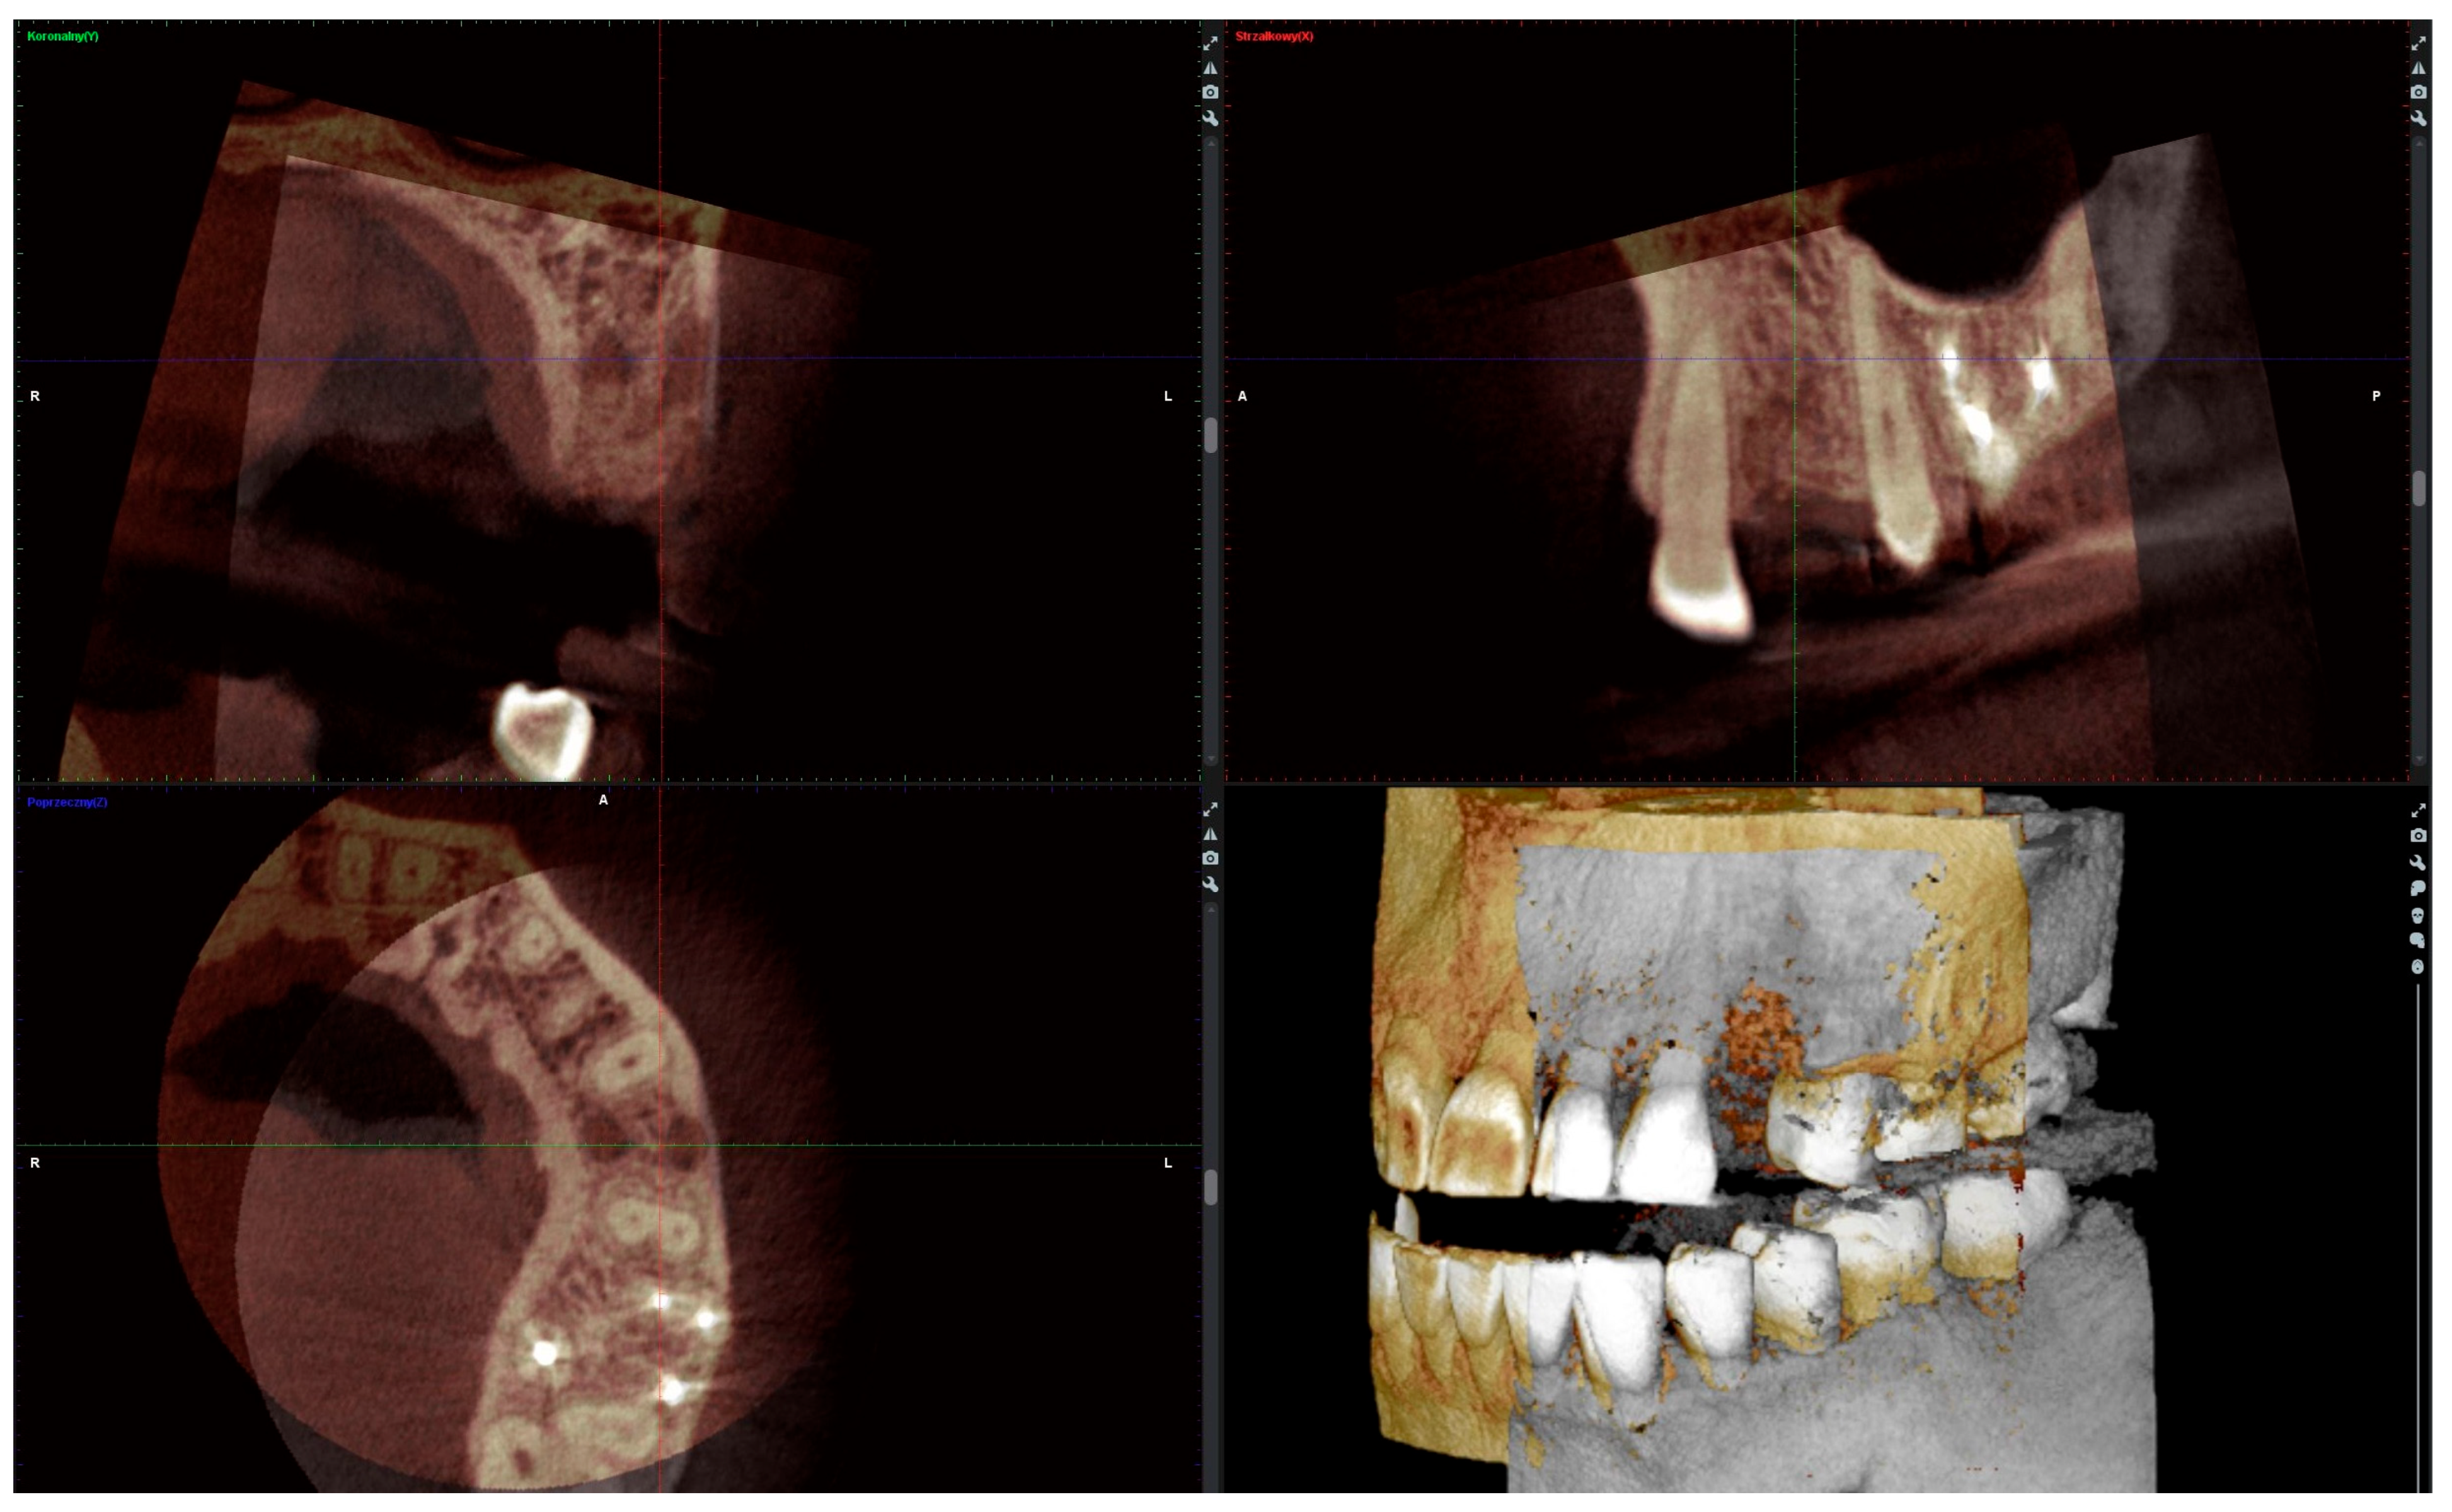

Six months after the socket preservation procedure, another CBCT with a 5 × 5 cm FOV was performed to plan the placement of the implant in the augmented site (Figure 2A).

Figure 2.

(A) Alveolar ridge after 6 months of healing; (B) bone biopsy with trephine; (C) obtained trepanobiopsy; (D) implant secured with cover screw; (E) screw-retained crown restoration.

2.4. Radiographic Analysis

The radiographic analysis consisted of alveolar ridge dimension measurements taken 1 week and 6 months post socket preservation surgery. The measurements were made using the Romexis software provided by the Planmeca company. The superimposition of the radiographic images was created automatically by selecting 3 reference points, most often the incisal edges and cusps of adjacent teeth. Afterward, the images were manually corrected (Figure 3). The above-mentioned steps ensured the repeatability of the measurements carried out on sagittal planes, which were oriented in such a manner that the buccal bone plate was parallel to the long axis. The measurements were made in the central part of the alveolus. The distance between the buccal and palatal bony plates was measured at the alveolar crest, the bottom of the alveolus, and midway between these two points (Figure 4A). The height was measured from the bottom of the alveolus to the top of the buccal and palatal bony plates, respectively (Figure 4B).

Figure 3.

Superimposition of radiographic images.

Figure 4.

(A) Alveolar ridge width measurements: coronally (red line), midpoint (yellow line) and apically (green line); (B) alveolar ridge height measurements: buccally (blue line) and palatally (pink line).

Bone optical density was measured in Hounsfield units (HU) using ImageJ software (version 1.53k, Wayne Rasband and contributors, National Institutes of Health, Kensington, MD, USA). The readings were taken on the horizontal plane in the central part of the alveoli 7 days and 6 months after surgery (Figure 5). If an interradicular septum was present in the central part of the socket, measurements were taken more coronally to reduce the risk of bias.

Figure 5.

Radiographic optical density of bone measured using ImageJ software. The yellow circle represents the ROI where the measurements were taken, and the red circle represents the positioning pin used for orientation during the measurements.